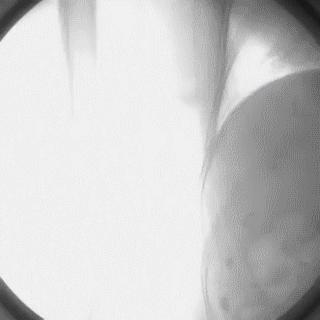

2014年,Patel T等首先采用球囊辅助通过技术(Balloon-assisted tracking,BAT),用于通过桡动脉途径中扭曲、细小节段(包括严重痉挛节段)(图1-2)。

图1

图2 BAT技术应用实例1。52岁女性患者冠脉严重痉挛(A),注射2次鸡尾酒后仍未缓解(B),采用BAT技术(C),顺利介导7F指引导管通过桡动脉严重痉挛节段(D)